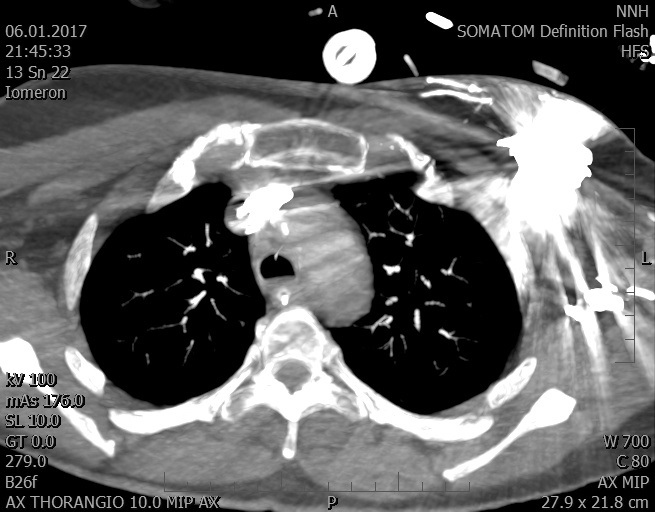

Video 1 - Akutní koronarografie prokázala normální nález na věnčitých tepnách s výjimkou suspekce na lehký spasmus na pravé koronární tepně.Echokardiograficky byla zjištěna těžká dysfunkce dilatované levé komory s nezvětšenou pravou komorou (video 2).

Video 2 - Echokardiograficky byla zjištěna těžká dysfunkce dilatační levé komory s nezvětšenou pravou komorou.Pro nejasnou příčinu zástavy jsme provedli i vyšetření výpočetní tomografií (CT), které vyloučilo plicní embolizaci (série 1 - soubory na konci článku). V den přijetí při přetrvávající oběhové nestabilitě byla nemocná opakovaně defibrilována pro fibrilaci komor se stabilizací rytmu po podání amiodaronu a mesocainu. Dle hemodynamických měření se jednalo o těžký kombinovaný šok. Vstupní laboratorní vyšetření bylo bez větších pozoruhodností. Posléze jsme doplnili anamnézu od příbuzných a zjistili, že pacientka užila do dvou hodin před srdeční zástavou první tabletu amoxicilinu na lehký respirační infekt. Při nevýtěžnosti vstupních vyšetření a nových anamnestických informacích jsme doplnili 14 hodin po kolapsu vyšetření koncentrace tryptázy v séru, která byla extrémně zvýšena (tabulka 2), což nás vedlo k podezření na anafylaxi.